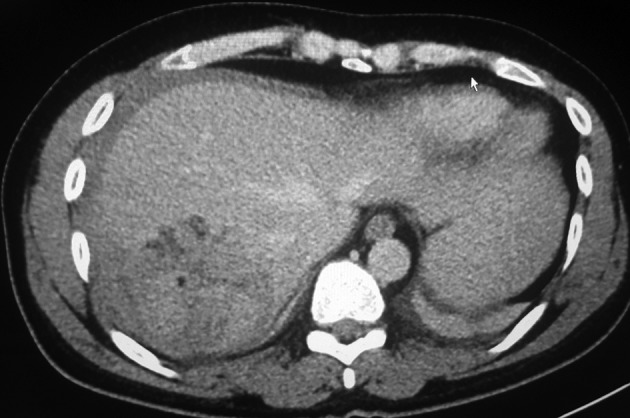

Background: Gossypiboma is the term for forgotten textile products such as a surgical sponge and compress in the body cavity after a surgical procedure.

Conclusions: Gossypiboma may not be symptomatic for many years or could be symptomatic for a short duration of time. Besides being a rare surgical complication, gossypiboma can lead to serious morbidity and mortality that may cause medico-legal problems. Diagnosis with imaging methods is difficult.